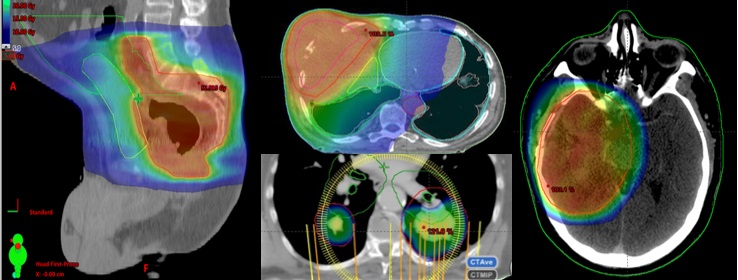

This picture shows a thermal scan